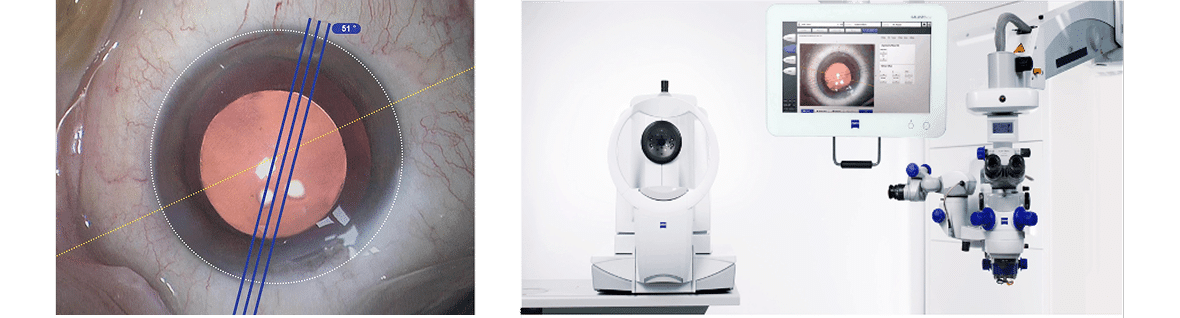

Our clinic excels in cataract management, offering the full range of cataract surgery options. We emphasize detailed pre-operative planning to ensure our patients have all the information they need to make the best decision on their cataract surgery and that the outcomes we deliver are tailored to the specific visual needs of each patient with their unique visual requirements.

1. Applying the latest version of imaging technology called swept-source optical coherence tomography

a. Patented Cornea-to-Retina Scan: so unusual eye geometries such as tilt or

decentering of the cataract can be detected

b. Unique Fixation Check: this feature minimises risk of inaccuracies because patients find it difficult focusing on the target during imaging

c. Integrates with Zeiss Cataract Suite: measurements taken for cataract surgery can be exported to the operating microscope providing reference image for intraoperative matching with live eye image during cataract

surgery

d. Central Topography with more insights: the IOLMaster® 700 from ZEISS

measures Central Topography. It allows easy reading of central corneal shape information to increase precision in cataract surgery.

e. The Total Keratometry (TK) of ZEISS IOLMaster 700 allows us to directly measure the posterior corneal surface using SWEPT Source OCT. In a study the exclusive Barrett True K with TK formula improved the outcome prediction compared to the Barrett True K with Classic Ks within ±0.5 D by >12 % (p =0.04) in post-myopic LASIK eyes.

2. The Zeiss IOL Master is the 700 allows for very precise calculations needed for

determining: the right intraocular lens implant to use in your cataract surgery

3. Precise and efficient markerless intraocular lens alignment during cataract surgery

With this system, manual marking for precise Toric Intraocular Lens alignment is replaced by the Zeiss CALLISTO computer assisted alignment which allows for assistance functions projected directly into the surgeon’s microscopic view2. At Hesed Eye we have invested in the IOL MASTER 700 which integrates seamlessly with the CALLISTO system in the operating theatre for surgery.